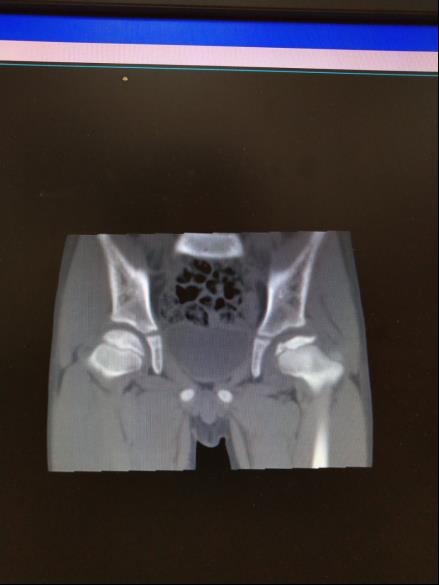

儿童股骨头缺血性坏死

儿童股骨头缺血性坏死行粗隆下内翻截骨钢板内固定治疗,增加股骨头包容,效果满意。图是CT片